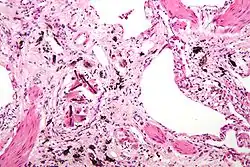

Plasticosis is a pathological wound healing in which connective tissue replaces normal parenchymal tissue to the extent that it goes unchecked, leading to considerable tissue remodelling and the formation of permanent scar tissue. Repeated injuries, chronic inflammation and repair are susceptible to fibrosis where an accidental excessive accumulation of extracellular matrix components, such as the collagen is produced by fibroblasts, leading to the formation of a permanent fibrotic scar.[3][4]

Plasticosis is found to cause increased collagen prevalence in the tubular glands and submucosa, and widespread scar tissue formation across the whole organ, leading to extensive reorganisation and tissue damage, and potentially a loss of tissue function. Since tubular glands produce mucus to protect the epithelium, as well as fluids that are crucial for digestion and nutrient absorption, plasticosis may affect the ability of birds to prevent injury or infection in the stomach and reduce stomach function. Excessive scar tissue formation in the stomach wall and loss of rugae induced by plastics may also reduce the ability of the stomach to expand, potentially reducing stomach capacity and function. Plasticosis has been compared to asbestosis and silicosis, where plastic acts a similar persistent irritant leading to fibrosis.[10][11]